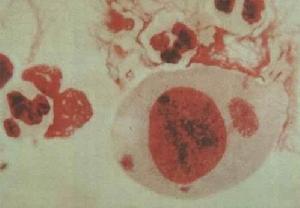

菌質體菌質體呈多形性,有球狀、球桿狀、棒狀、長絲狀和不規則狀。大小相差懸殊,最小的呈球形,直徑80~300nm,可通過濾菌器。革蘭氏染色陰性。電子顯微鏡下,菌質體的細胞膜由兩層蛋白質膜和一層脂膜組成。細胞質內有核糖體、雙股DNA、可溶性RNA(見圖[菌質體模式圖])。菌質體一般呈厭氧生長,有些株在有氧條件下亦生長良好。與病毒不同處為能在無活細胞的瓊脂培養基上生長。在含5~10%和相對濕度80~90%的大氣環境中生長較佳。來自靈長類的菌質體如口型菌質體、唾液菌質體等,大多在含95%氮和5%環境中才能生長及分離。菌質體的生長繁殖速度較細菌緩慢,最快需24~48小時,一般需7~14天,生長緩慢的需21~30天。菌質體沒有細胞壁,易被脂溶劑如乙醚、氯仿等以及酒精和常用消毒劑如石炭酸、甲醛等溶解和滅活。對熱和乾燥敏感,不耐酸。對干擾蛋白質合成的抗生素如四環素敏感,但對干擾細胞壁合成的抗生素如青黴素則不敏感。菌質體在自然界中分布很廣,許多動物、昆蟲和植物都能儲存和攜帶菌質體。

3.直接塗片鏡檢:取咽分泌物、痰、呼吸道教膜或其他部位標本做塗片,進行GZmesa染色,原體染成紅色,始體染成深藍色。沙眼衣原體包涵體因含有糖原,801染色染成褐色。